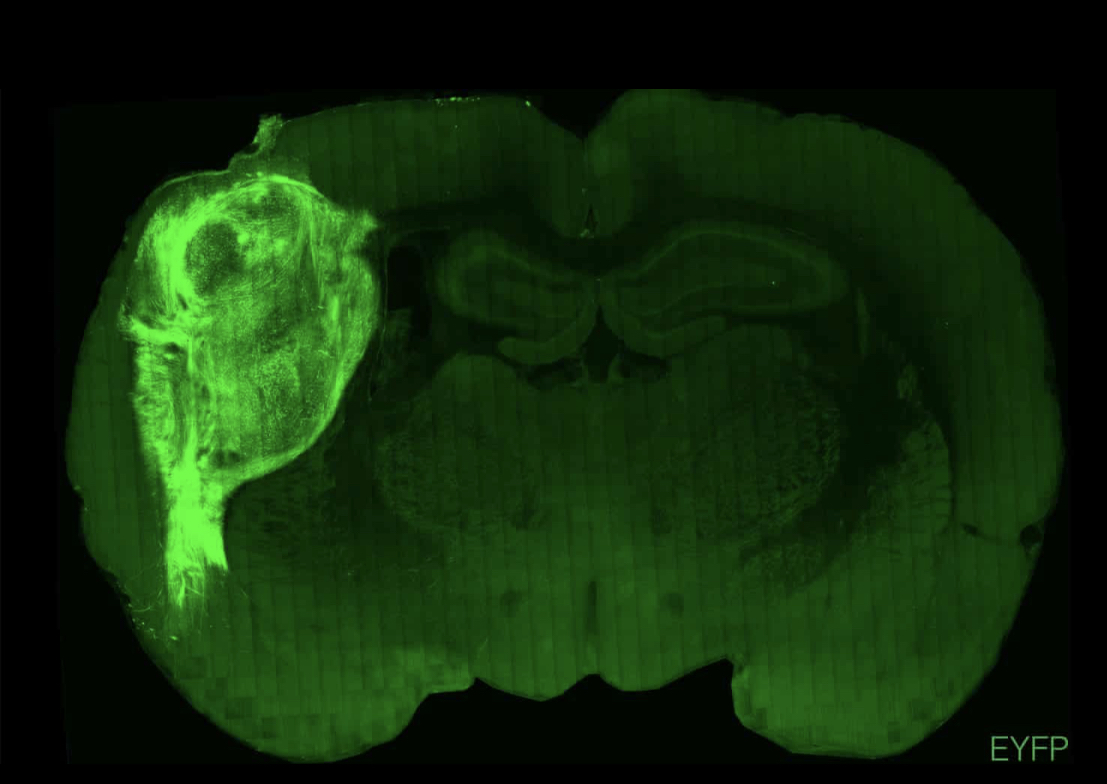

由斯坦福大学研究人员领导的这项最新成果10月12日发表在《自然》(Nature)杂志上。通过将人类干细胞培育的神经组织植入大鼠大脑中,研究人员相当于建立了一个神经类器官动物模型平台,可用于模拟人类大脑的发育和疾病机制。

为了克服这些问题,斯坦福大学的精神病学教授Sergiu Pasca和他的同事在培养皿中培养了人脑类器官,直到这些类器官长出了50万至100万个神经元后,将它移植到新生大鼠大脑中的体感皮层区域,该区域可以控制大鼠胡须运动等触觉。5个月后,核磁共振扫描显示,类脑组织已经发育了六至八倍。